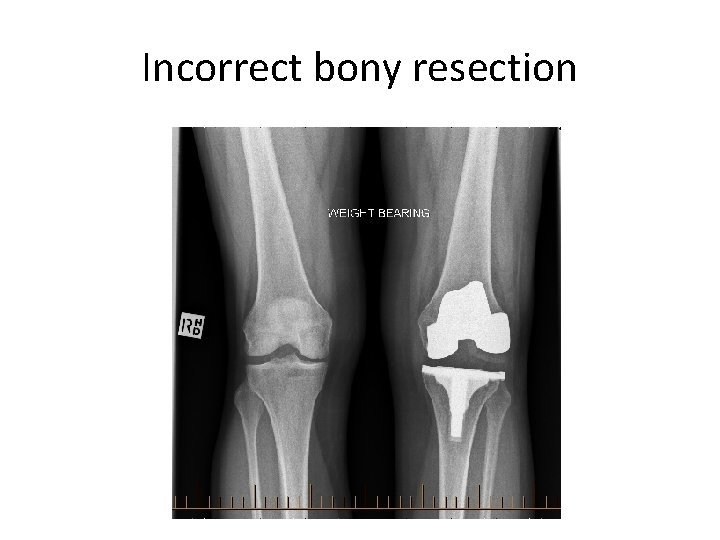

Incorrect bony resection

Reasons for instability Knee replacement • Ligament deficiency excessive release transection • Improper gap balancing undersized femoral component (loose flexion gap) excessive bony resection inadequate thickness of polyethylene liner • Malalignment of components

Reasons for instability Knee replacement • Ligament deficiency excessive release transection • Improper gap balancing undersized femoral component (loose flexion gap) excessive bony resection inadequate thickness of polyethylene liner